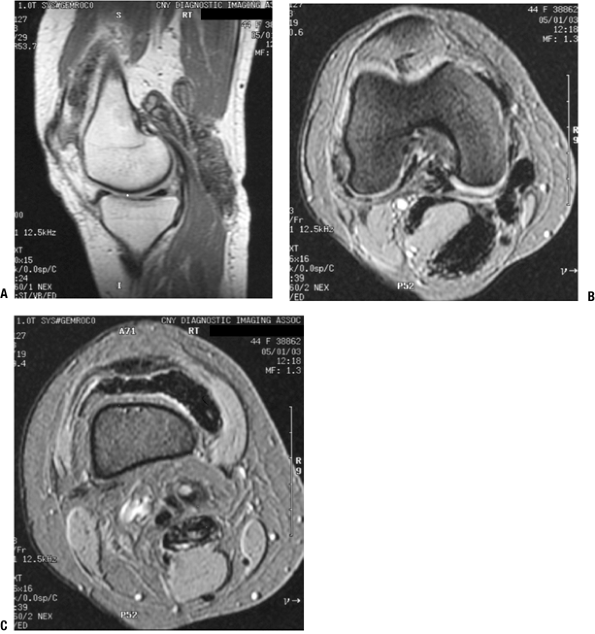

Nonspecific MRI features (Fig. 11-15)P.277

Figure 11-15 Giant cell tumor of tendon sheath shows a soft tissue shadow on plain lateral radiograph (A), hypointense signal on axial T1-weighted MRI (B), hyperintense signal on axial T2-weighted MRI (C), and gadolinium enhancement on post-contrast fat-suppressed T1-weighed sagittal MRI (D).-

T1-weighted images: hypointense to slightly hyperintense to muscle

-

T2-weighted images: hypointense to hyperintense to muscle

Heterogeneous due to hypointense areas

Diffuse contrast enhancement

Usually plain radiographs and MRI are sufficient for these small masses.